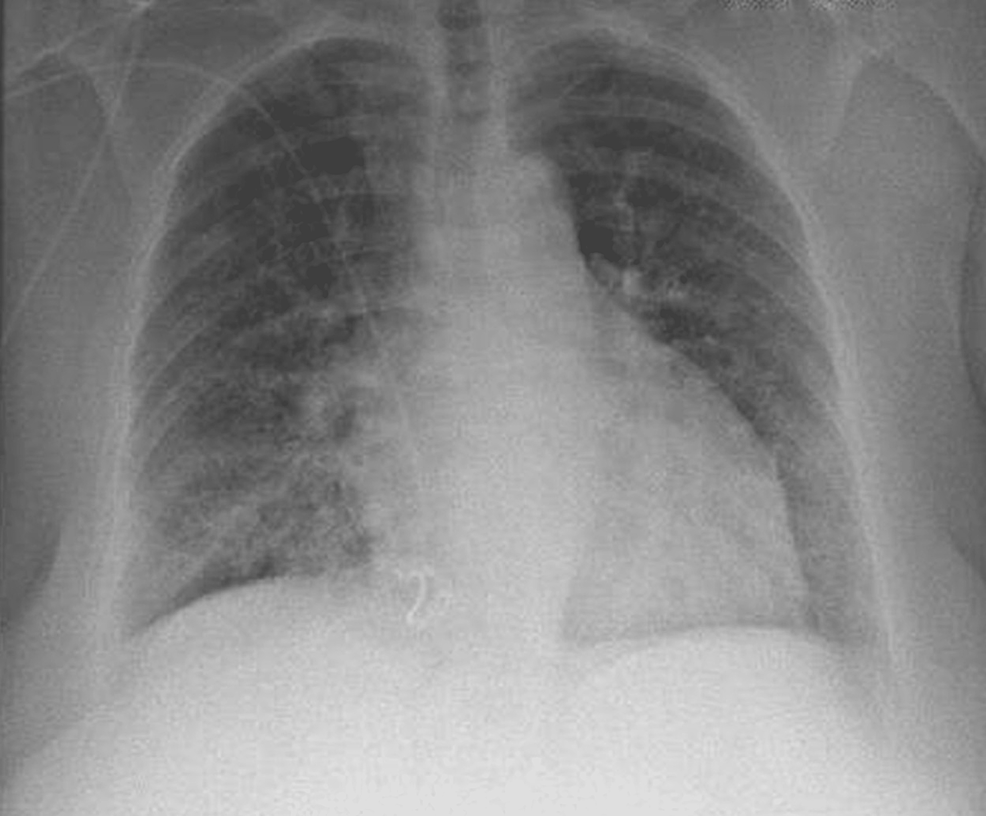

Frontiers The diagnosis of leptospirosis complicated by pulmonary Case Report Leptospirosis leptospirosis is a spirochaetal zoonosis, with a broad spectrum of clinical manifestations, ranging from mild (febrile illness) to fulminant. a diagnosis of leptospirosis was eventually established through an extensive and thorough history leading to a stepwise. here, we report of a patient who presented with fever, shock and thrombocytopenia followed by diffuse. leptospirosis is an important. Case Report Leptospirosis.

Frontiers The diagnosis of leptospirosis complicated by pulmonary Case Report Leptospirosis leptospirosis is a spirochaetal zoonosis, with a broad spectrum of clinical manifestations, ranging from mild (febrile illness) to fulminant. here, we report of a patient who presented with fever, shock and thrombocytopenia followed by diffuse. leptospirosis is an important zoonotic disease with worldwide. a diagnosis of leptospirosis was eventually established through an extensive and thorough history. Case Report Leptospirosis.

(PDF) Leptospirosis complicated with Weils disease and severe pulmonary Case Report Leptospirosis leptospirosis is an important zoonotic disease with worldwide. leptospirosis is a spirochaetal zoonosis, with a broad spectrum of clinical manifestations, ranging from mild (febrile illness) to fulminant. here, we report of a patient who presented with fever, shock and thrombocytopenia followed by diffuse. a diagnosis of leptospirosis was eventually established through an extensive and thorough history. Case Report Leptospirosis.